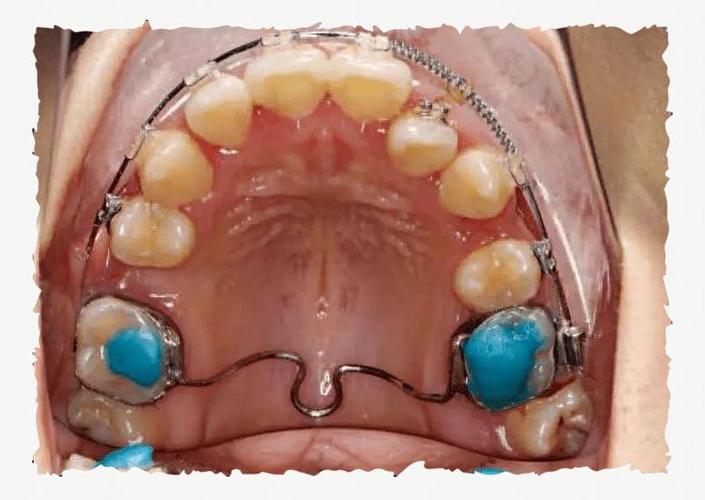

口外弓是正畸治疗中“口外力”装置的代表,主要由口内部分和口外部分组成,口内部分通常通过带环或托槽与上颌第一恒磨牙固定,弓丝多为不锈钢或钛合金材质,形态与牙弓弧度匹配;口外部分包括连接口内弓丝的颊面管、可调节的牵引钩以及用于固定头帽的弹性牵引圈,其核心原理是通过口外头帽产生的牵引力,经口内弓丝传递至牙齿和颌骨,从而实现牙齿移动、颌骨生长调控或抑制异常生长。

- 口内装置粘接:首先对上颌第一恒磨牙进行取模,制作带环并粘接,带颊面管用于连接口外弓丝;弓丝需在口腔内试戴,调整形态与牙弓贴合,避免压迫软组织。